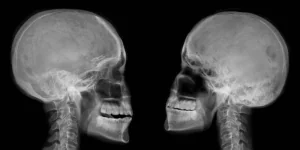

Facial Palsy incidence following inferior alveolar nerve block: A Questionnaire Survey Research and analysis